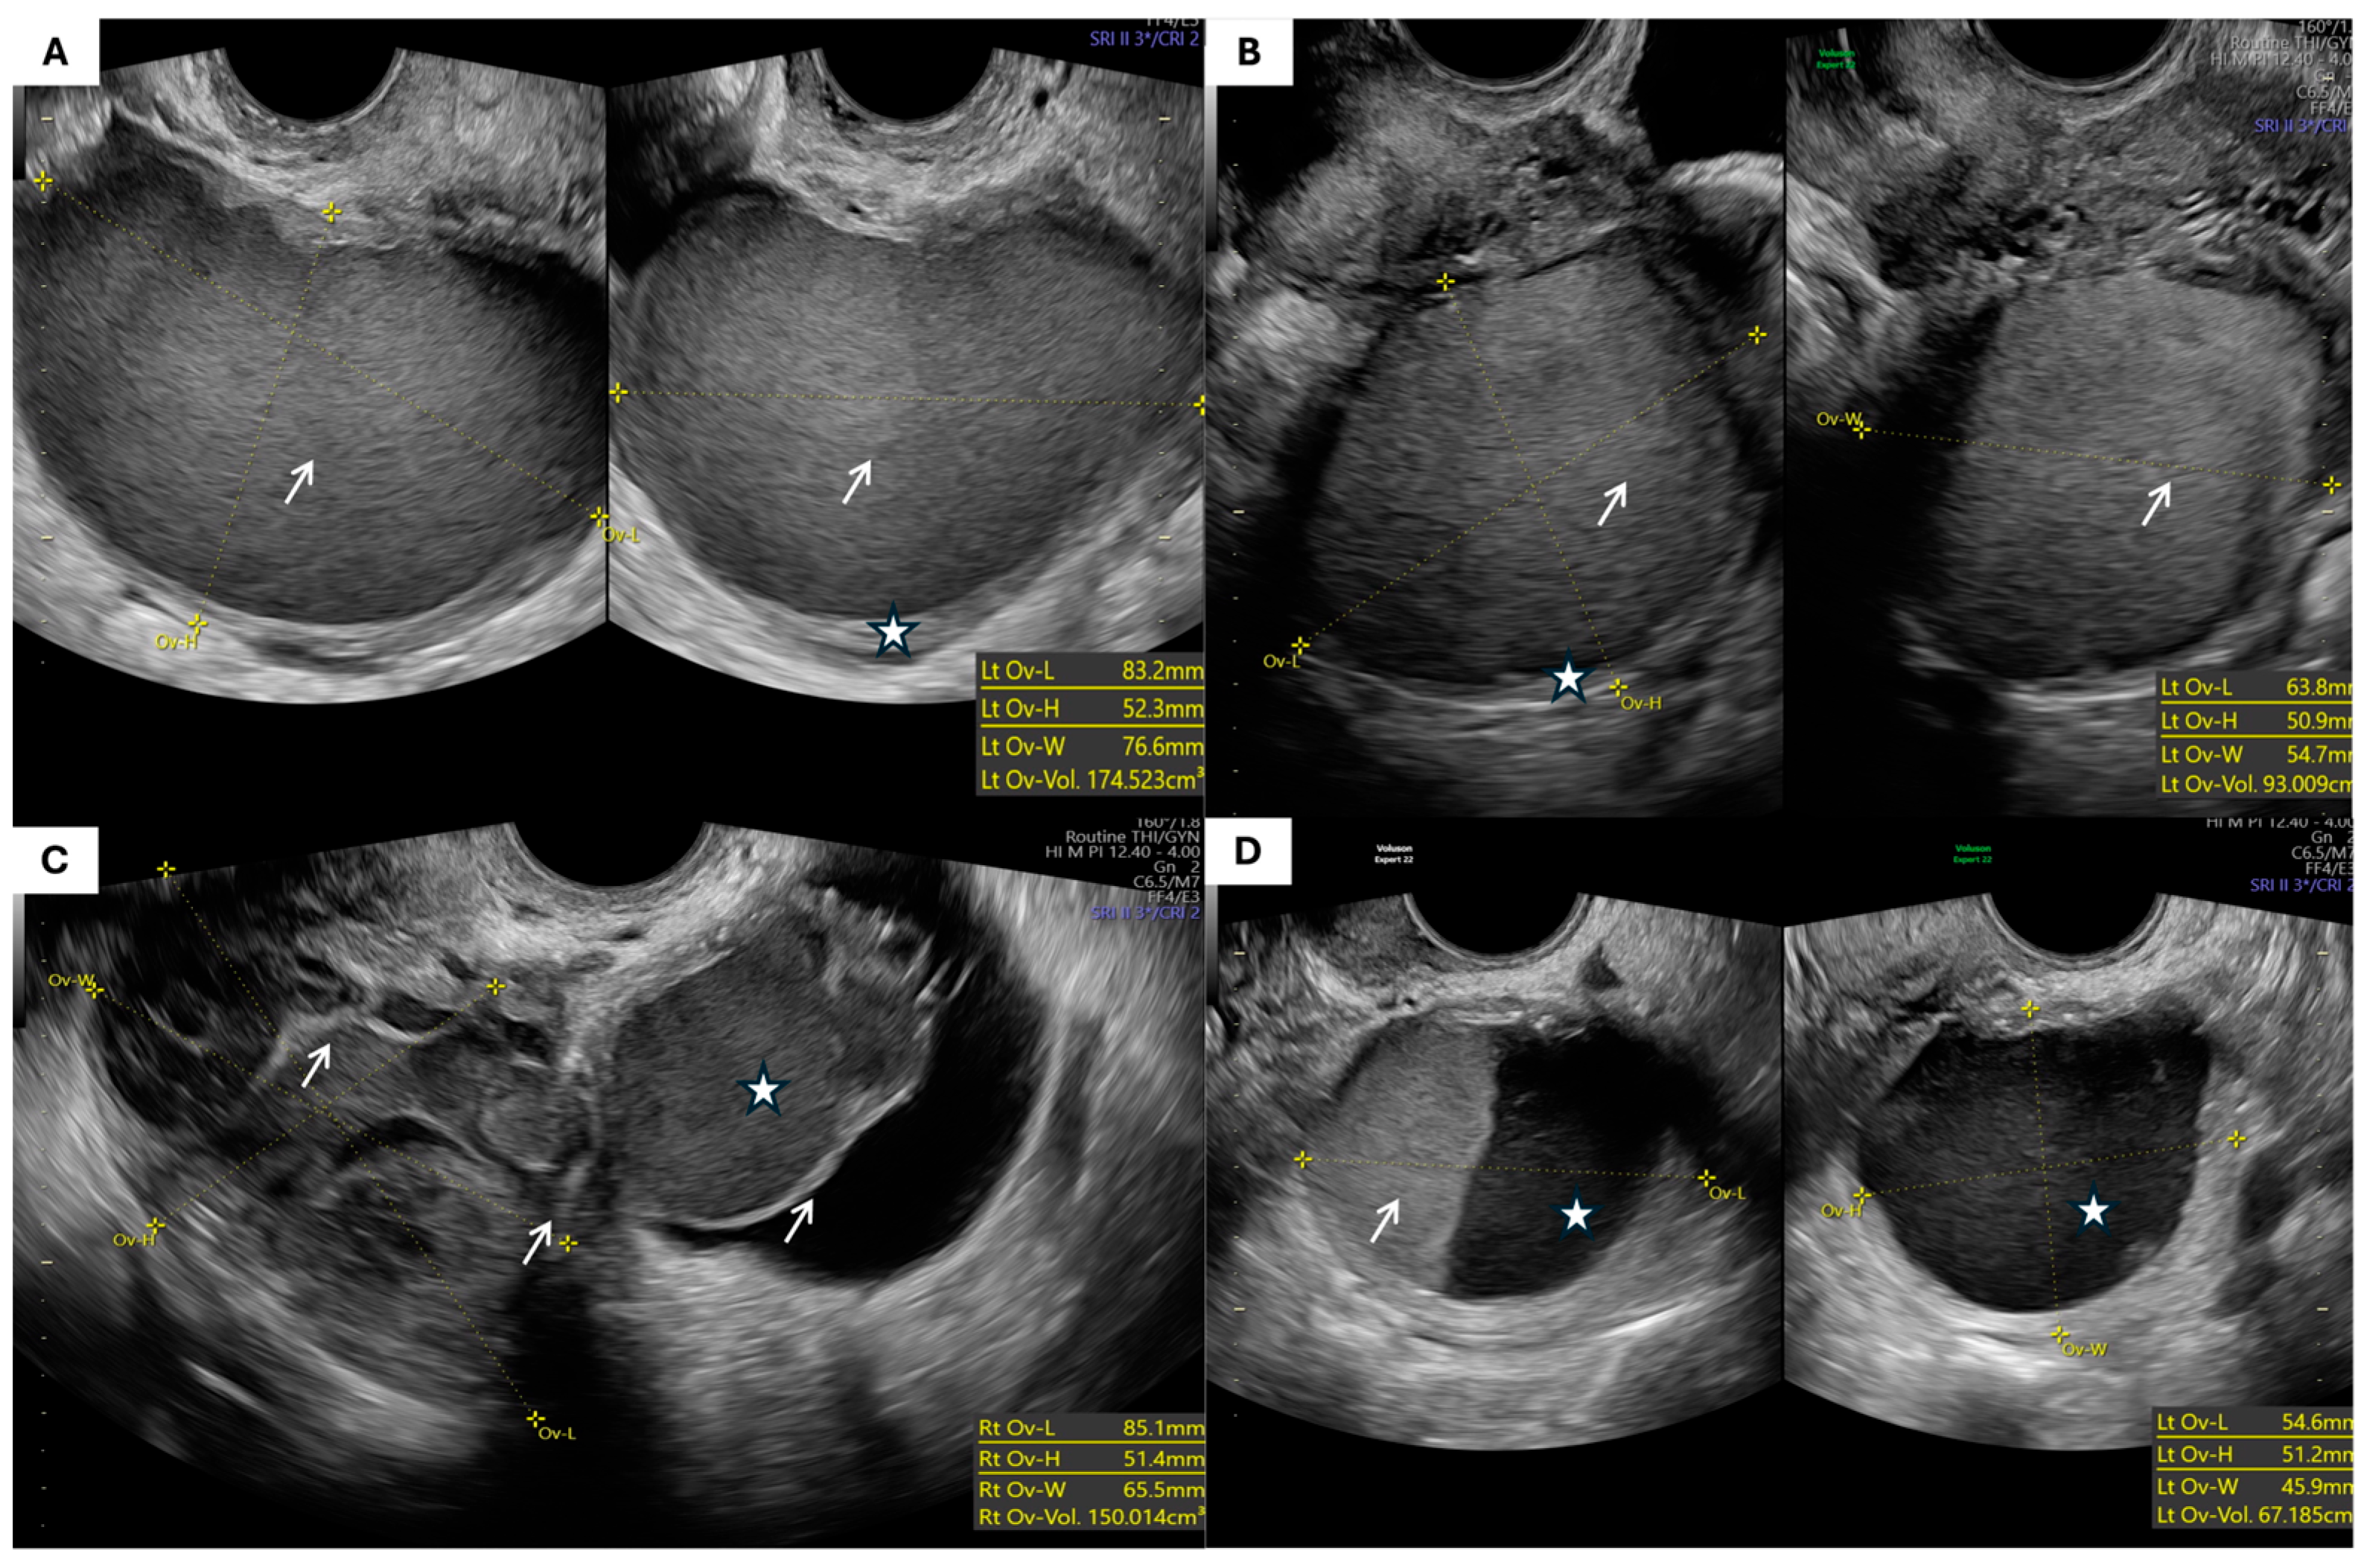

- Morphological Parameters: The morphological assessment included the largest tumor diameter, volume (calculated using the prolate ellipsoid formula: length × height × width × 0.523), laterality, capsule thickness, and internal echogenicity (categorized as anechoic, homogeneous low-level “ground-glass”, hyperechoic, or mixed/heterogeneous). The presence of septa, papillary projections, solid components, acoustic shadowing, free fluid in the pouch of Douglas, and signs of tumor fixation were also recorded.

| The largest tumor dimension (mm), mean ± SD | 78.2 ± 3.3 | 81.9 ± 4.3 | 0.6 |

| Tumor volume (cm3), mean ± SD | 247.9 ± 65.2 | 254.3 ± 75.3 | 0.7 |

| Tumor capsule thickness (mm), mean ± SD | 2.87 ± 1.1 | 2.9 ± 1.1 | 0.9 |

| Morphological Type (IOTA Terminology) | Endometriomas (n = 55) | % | Teratomas (n = 49) | % | p-Value |

| Unilocular cyst with ground-glass echogenicity | 25 | 45.5% | 0 | 0% | <0.001 * |

| Unilocular solid cyst with hyperechoic content | 1 | 1.8% | 10 | 20.4% | |

| Multilocular cyst | 8 | 14.5% | 5 | 10.2% | |

| Multilocular solid cyst | 9 | 16.4% | 25 | 51.0% | |

| Cyst with papillary projections (unilocular or bilocular) | 1 | 1.8% | 1 | 2.0% | |

| Solid tumor | 3 | 5.5% | 4 | 8.2% | |

| Other/not otherwise specified | 8 | 14.5% | 4 | 8.2% |